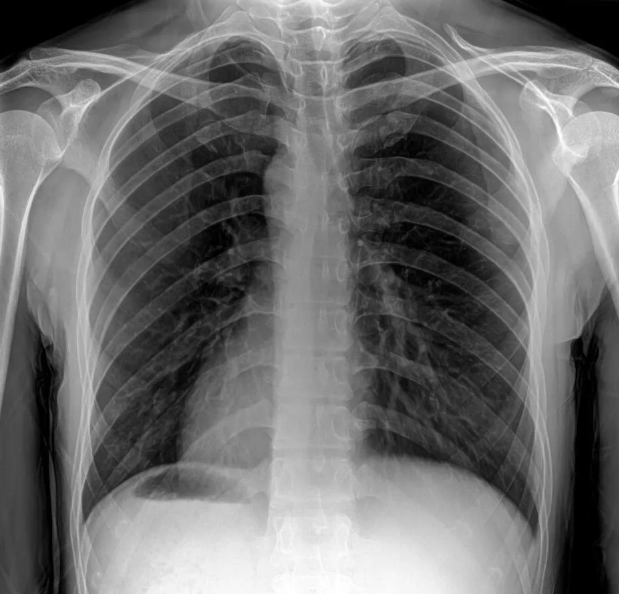

- Focused Grids: Lead strips are angled to converge toward a focal point (aligning with the X-ray tube’s focus). They offer superior scatter filtration compared to parallel grids, making them the standard choice for imaging thick body parts (e.g., chest, abdomen)—the most common use case in radiology departments.